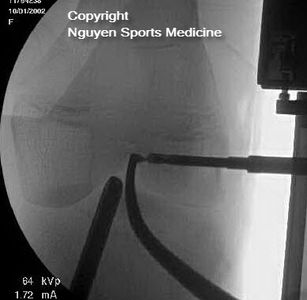

- Pediatric ACL Surgery